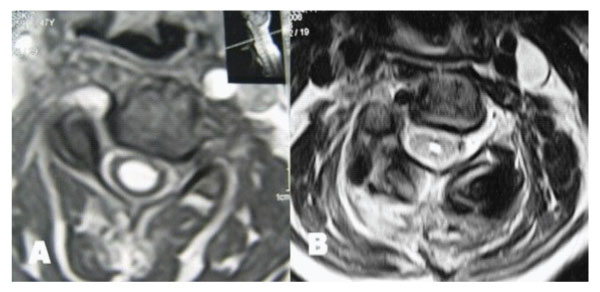

Figure 4: T2 weighted axial MRIs taken at C5 level demonstrating resolution of syringomyelic cavity. A: Preoperative. B: Postoperative.

Antero-posterior diameter of foramen magnum was 20 mm; no bony compression to neural structures including odontoid process was detected, however anterior subarachnoid space could not be seen at the level of brain stem. MR angiography disclosed aplasia of left vertebral artery with a nearly normal trace of the right vertebral artery. The patient was treated by a posterior fossa decompression. In the operation, suboccipital craniectomy was performed. The right lamina of the atlas was also removed. Dural surface became expanded and pulsatile suggesting foramen magnum stenosis. CSF flow was observed after opening the dura mater. A large duraplasty was made with dural graft to maintain the CSF flow. Following the decompression and large duraplasty, occipital cervical fusion using C2 laminar screwing was performed. Post-operative period was uneventful, spasticity and weakness of the extremities and hyperreflexia improved. MR examination obtained six months after the operation showed the resolution of the syringomyelia [Figure 3,4].